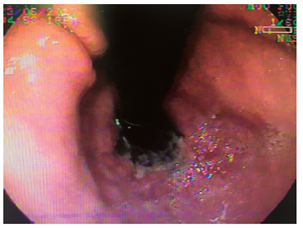

Mujer de 79 años, que consulta por urgencias por melanemesis y alteración de la conciencia. Como antecedente presentaba meningioma resecado, con síndrome convulsivo secundario, hipertensión arterial no controlada y enfermedad pulmonar obstructiva crónica. En los exámenes presentaba leucocitosis con neutrofilia (89 %); creatinina de 1,84 mg/dL, hipocloremia (92 mEq/L) e hiponatremia (129 mEq/L). La endoscopia mostró esfacelo del epitelio esofágico en los dos tercios inferiores y sangrado difuso en la capa (Figuras 1, 2, 3 y 4), sin cambios en el calibre. Se desconoce su evolución y su desenlace.